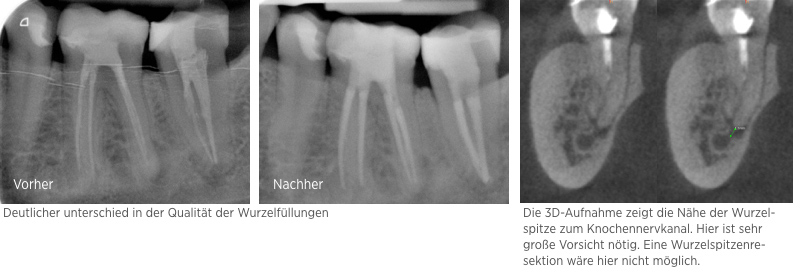

Fallbeispiel: Zahn 15 mit starker Krümmung

Jeder Zahn ist einzigartig – in diesem Fall zeigte sich Zahn 15 mit einer starke Wurzelkrümmung. Trotz der starken Krümmung konnte eine Wurzelkanalbehandlung durchgeführt werden und somit auch die Brücke erhalten werden.

Fallbeispiel: Molarenrevision mit Seitenkanal

Werden im Rahmen einer Wurzelkanalbehandlung nicht alle Bereiche innerhalb des Wurzelkanalsystems ausreichend gereinigt, kann es zu persistierenden Infektionen kommen. In diesem Fall war die persistierende Infektion auf einen feinen Seitenkanal zurückzuführen – mit einer Revisionsbehandlung und gründlicher Reinigung des Wurzelkanalsystems können auch solche persistierenden Infektionen erfolgreich behandelt werden!